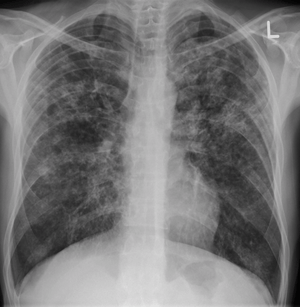

Chest X ray showing miliary tuberculosis

Miliary tuberculosis is a form of tuberculosis that is characterized by a wide dissemination into the human body and by the tiny size of the lesions (1–5 mm). Its name comes from a distinctive pattern seen on a chest radiograph of many tiny spots distributed throughout the lung fields with the appearance similar to millet seeds—thus the term "miliary" tuberculosis. Miliary TB may infect any number of organs, including the lungs, liver, and spleen.[2] Miliary tuberculosis is present in about 2% of all reported cases of tuberculosis and accounts for up to 20% of all extra-pulmonary tuberculosis cases.[3]

Testing for miliary tuberculosis is conducted in a similar manner as for other forms of tuberculosis, although a number of tests must be conducted on a patient to confirm diagnosis.[5] Tests include chest x-ray, sputum culture, bronchoscopy, open lung biopsy, head CT/MRI, blood cultures, fundoscopy, and electrocardiography.[11] The tuberculosis (TB) blood test, also called an Interferon Gamma Release Assay or IGRA, is a way to diagnose latent TB. A variety of neurological complications have been noted in miliary tuberculosis patients—tuberculous meningitis and cerebral tuberculomas being the most frequent. However, a majority of patients improve following antituberculous treatment. Rarely lymphangitic spread of lung cancer could mimic miliary pattern of tuberculosis on regular chest X-ray. [16]